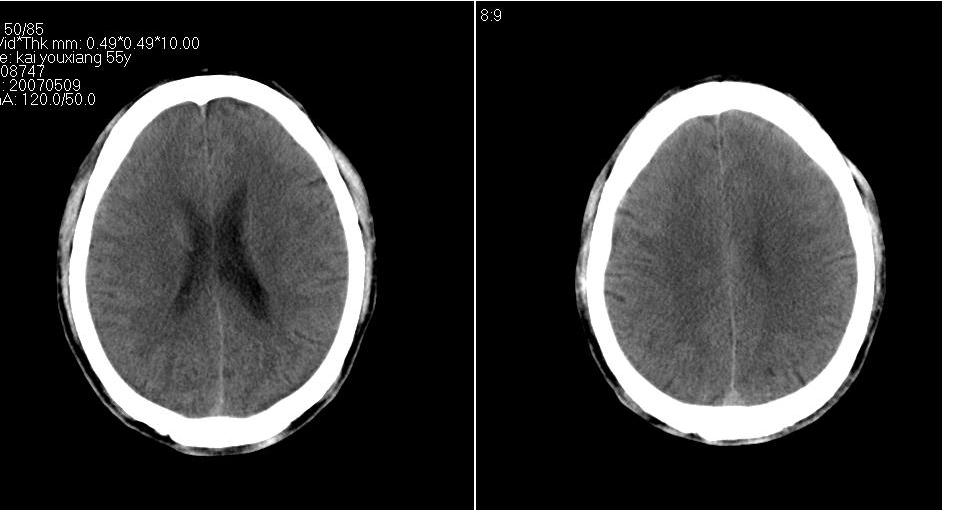

以下是引用tianhep在2007-5-9 19:53:00的发言:[br]这个部位多为苍白球钙化,苍白球钙化往往双侧对称。有外伤史而无症状。首先考虑为苍白球钙化。短期内复查一次就可。

以下是引用狙击手在2007-5-9 19:52:00的发言:[br]病灶边界模糊,外周无水肿带,无占位效应,无任何不适,考虑钙化。

以下是引用gyh6308在2007-5-9 21:10:00的发言:[br]这种病例我见过,是脑血管畸形所致的钙化,做cta可观察